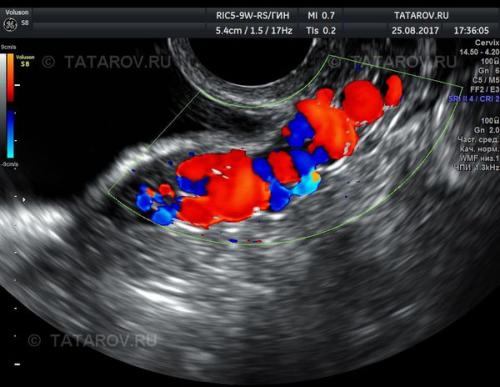

Основным методом диагностики, позволяющим предварительно установить диагноз ВБТ, является ультразвуковое исследование вен малого таза . Это безопасное и достаточно информативное исследование, позволяющее определить дальнейшую тактику диагностики и лечения. Обычно применяют сочетание трансабдоминального (через переднюю брюшную стенку) и трансвагинального (через влагалище) ангиосканирования. Трансабдоминально просматриваются яичниковые, подвздошные, нижнюю полую и почечные вены для определения их диаметров, венозных рефлюксов, поражения тромботическими процессами и исключения компрессионных синдромов.

Трансвагинально исследуют вены параметрия (части клетчатки малого таза, которая окружает матку), гроздевидных сплетений и аркуатных в ен (вен мышечной стенки матки). Вари козно изменённые вены представляют собой извитые, неравномерно расширенные конгломераты различного диаметра.